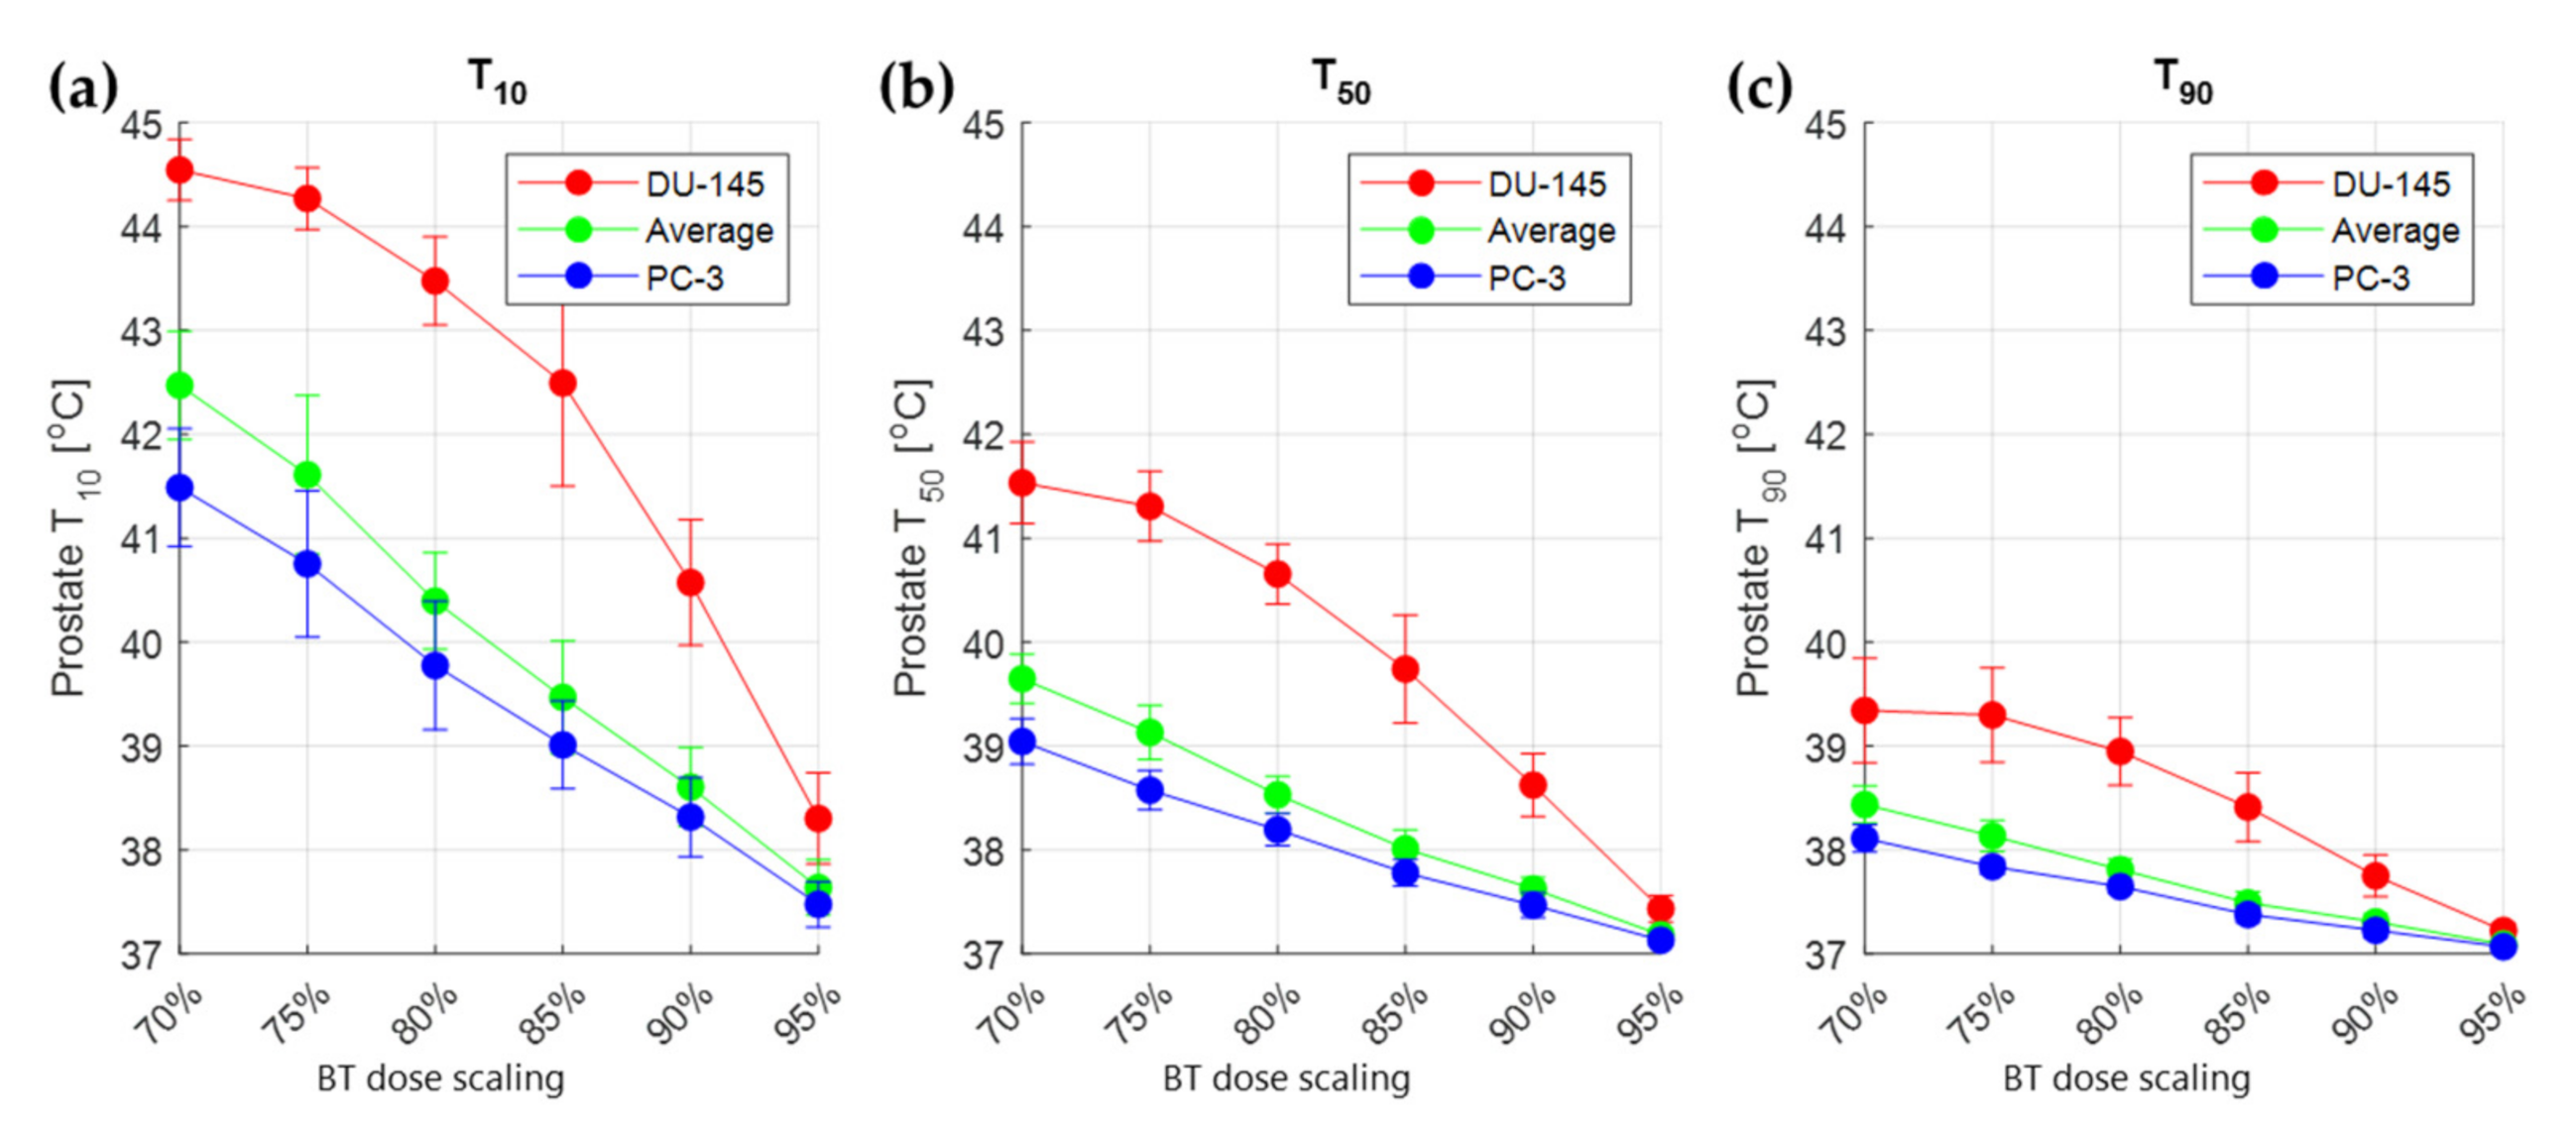

3.3. Treatment Planning Results

4. Discussion